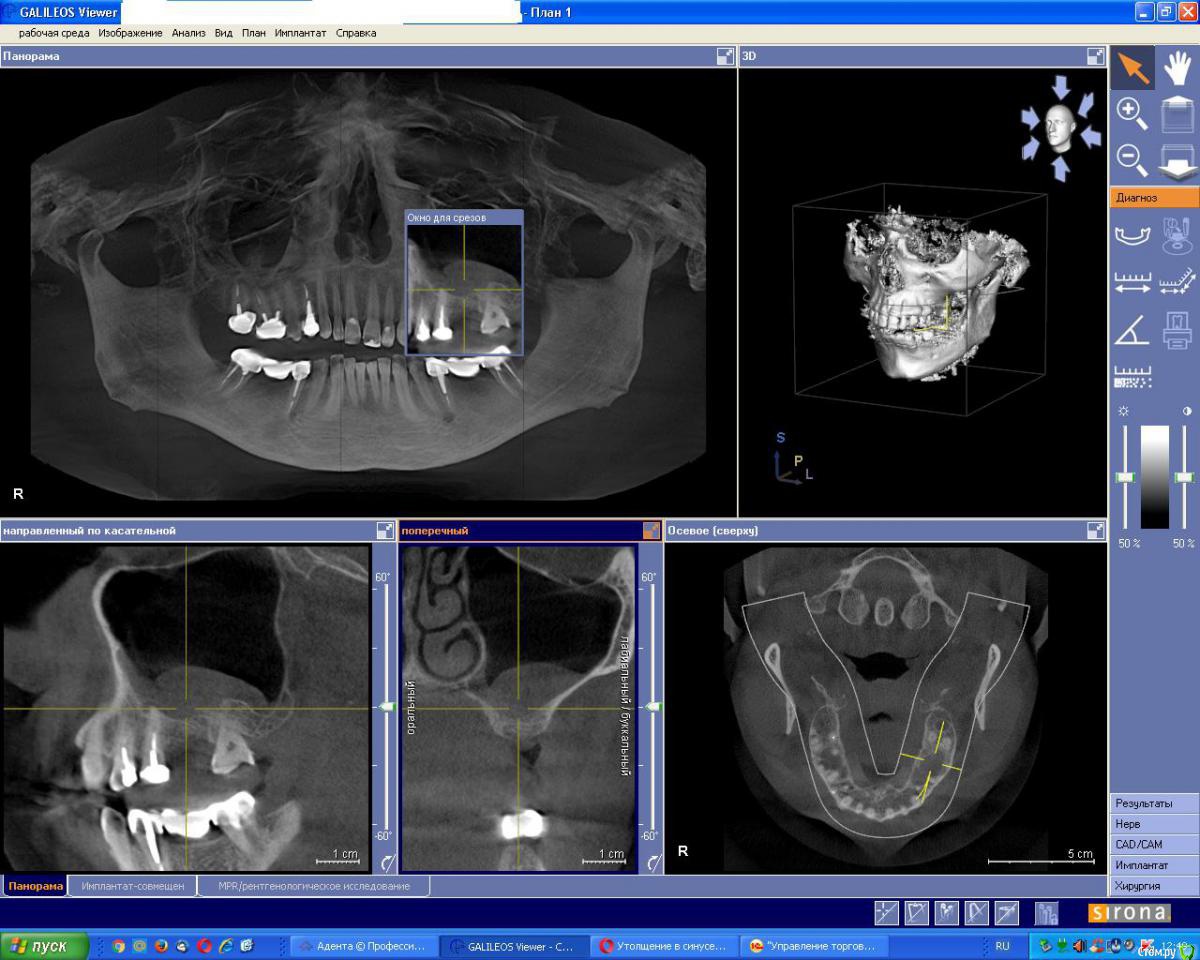

ivanov6988 Опубликовано 30 мая, 2017 Поделиться Опубликовано 30 мая, 2017 Добрый день. Дабы не плодить темы по тактике всяких утолщений продолжу здесь.Клкт через 6нед после удаления 1.7 Планирем синуслифт+импл в поз 1.7 1.5, Как бы вы поступили? Пойти крестально на синус в обл 15+ латерально окно для аспирации содержимого илисделать два окна выше/ниже иливообще отслаивать как при обычном ибо это не киста а полип Ссылка на комментарий

kamranchick Опубликовано 30 мая, 2017 Поделиться Опубликовано 30 мая, 2017 Добрый день. Дабы не плодить темы по тактике всяких утолщений продолжу здесь.Клкт через 6нед после удаления 1.7 Планирем синуслифт+импл в поз 1.7 1.5, Как бы вы поступили? Пойти крестально на синус в обл 15+ латерально окно для аспирации содержимого илисделать два окна выше/ниже иливообще отслаивать как при обычном ибо это не киста а полип все зависит от ваших манульных навыков, можно и аспирировать жидкость можно не аспирировать, я бы не аспирировал и пошел бы двух этапно, сначала синус, через 6 месяцев повторное кт и оценил бы ситуацию для последующей имплантации. и посмотрите может это все от 4 зуба, на мой взгляд целесообразно удалить зуб 4 и установить имплантат 4 - 6 так как в области 7 го зуба неровности, при выполнения синус лифтинга будут определенные риски, плюс на нижней челюсти длинный мост стоит, скорее всего не особо надежный Ссылка на комментарий

Bier Опубликовано 30 мая, 2017 Поделиться Опубликовано 30 мая, 2017 Добрый день. Дабы не плодить темы по тактике всяких утолщений продолжу здесь.Клкт через 6нед после удаления 1.7 Планирем синуслифт+импл в поз 1.7 1.5, Как бы вы поступили? Пойти крестально на синус в обл 15+ латерально окно для аспирации содержимого илисделать два окна выше/ниже иливообще отслаивать как при обычном ибо это не киста а полип Делается 2 доступа, если делать классически, через латеральное окно, то нужно вначале сделать доступ очень высоко, у самой вершины образования (небольшой, под размер слюноотсоса). Сначала аспирировать содержимое, потом вытянуть образование отсосом и пинцетом. После этого спокойно делать синуслифтинг с доступом несколько ниже. Либо крестально, но смысла уже нет крестальный доступ делать, раз уж лоскут все равно откинете. 1 Ссылка на комментарий

ivanov6988 Опубликовано 19 ноября, 2017 Поделиться Опубликовано 19 ноября, 2017 Делается 2 доступа, если делать классически, через латеральное окно, то нужно вначале сделать доступ очень высоко, у самой вершины образования (небольшой, под размер слюноотсоса). Сначала аспирировать содержимое, потом вытянуть образование отсосом и пинцетом. После этого спокойно делать синуслифтинг с доступом несколько ниже. Либо крестально, но смысла уже нет крестальный доступ делать, раз уж лоскут все равно откинете.Спасибо. КЛКТ контроль спустя 5мес. Раскрываем Ссылка на комментарий